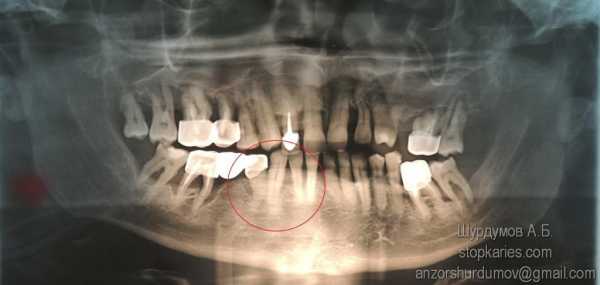

- Зубы мудрости – как и все зубы подвержены всему выше перечисленному. Так же для зубов мудрости чаще всего не хватает места и они длительно пытаются прорезаться, что сопровождается болевыми ощущениями. При частичном прорезывании пища скапливающаяся под нависающей над зубом десной может приводить к гнойным осложнениям (перекоронарит, переостит, абсцесс). В большинстве случаев зубы мудрости вырастаю в положении не характерном для всех остальных зубов, что может приводить к травмам щеки при жевании или воспалению слизистой между зубом мудрости и соседним ему коренным зубом.

На рентгенограмме ретенированные (не прорезывавшиеся) зуб мудрости — 38, 48